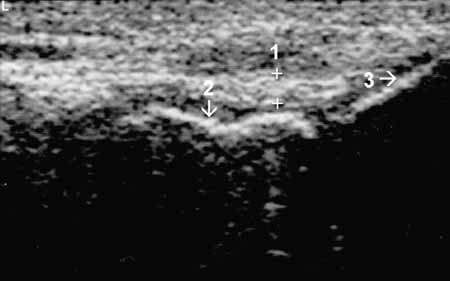

Рис. 8. Коленный сустав в норме. Наружная поверхность коленного сустава,

сагиттальная проекция. Наружная (малоберцовая) коллатеральная связка (1+), 2

— большеберцовая кость, 3 — головка малоберцовой кости.